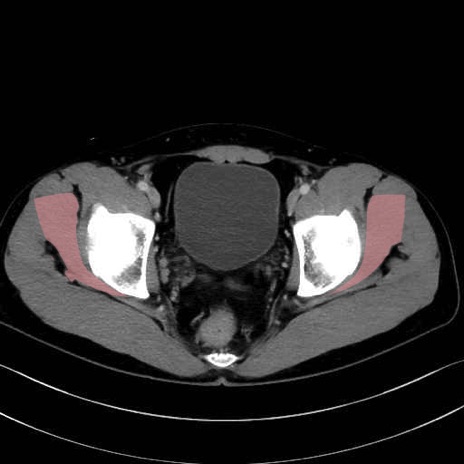

小殿筋 (Gluteus minimus)